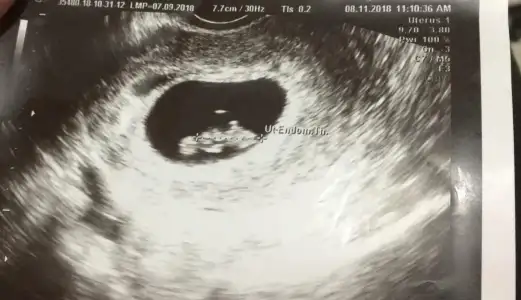

Vajinal ultrason bu.

• 9110170F-0898-4696-AA24-4B2641BB5DD3.webp

9110170F-0898-4696-AA24-4B2641BB5DD3.webp

41,9 KB · Görüntüleme: 63